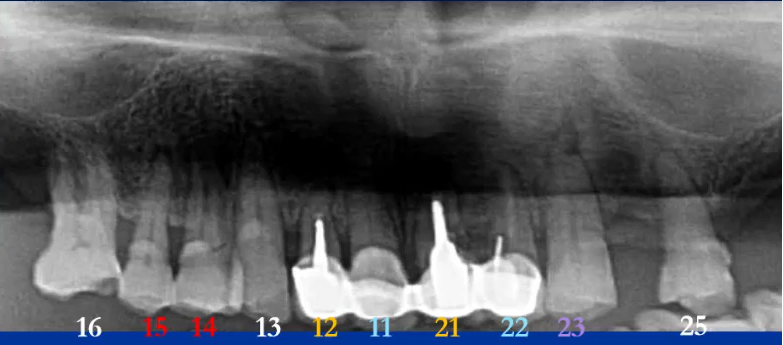

【病例5】

71岁,女性,右下颌后牙缺失要求种牙

曲断片:全面了解患者口腔情况

种植:缺牙位置、上颌窦、下颌神经管

牙周:牙槽骨、牙结石

牙体:龋坏、根尖炎、楔缺、合面磨耗

初步诊断及预判:结合临床检查,哪些重点检查;影像经验,14、15,12、21,23,11、22

曲面断层片怎么看口腔精读 | 一次性教你看懂曲面断层片!_https://www.jmylbn.com_新闻资讯_第61张

下颌种植主要判断:神经管走行及位置

左侧神经管下壁显示清晰,但上壁右侧神经管不清晰,前段疑似膨大。